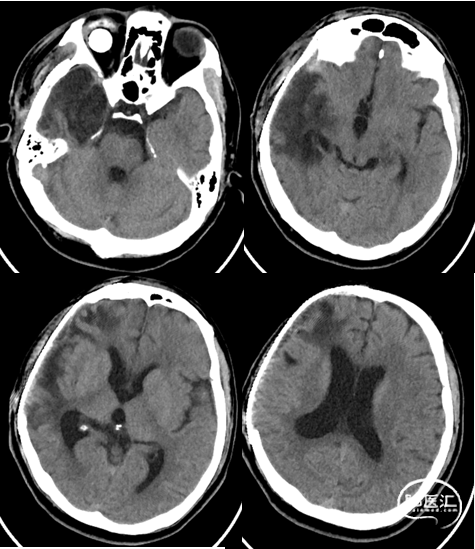

出院时影像

患者偶有烦躁、偏执、哭闹,可遵嘱动作,独立行走,无发热,无呕吐及四肢抽搐,大小便正常。

查体:神志清楚,左侧瞳孔直径2.5mm,对光反射灵敏,右眼眼球摘除术后,头部切口愈合良好,骨窗压力不高,双肺呼吸音粗,未闻及啰音,腹软,左侧肢体肌力4+级,右侧肢体肌力5级,肌张力正常,生理反射存在,病理反射未引出。

半年后颅骨修补前影像

颅骨修补后影像、随访

颅骨修补后1月预后情况:

神志清楚,精神状态正常,言语对答流利,定时定向力正常,四肢活动自如